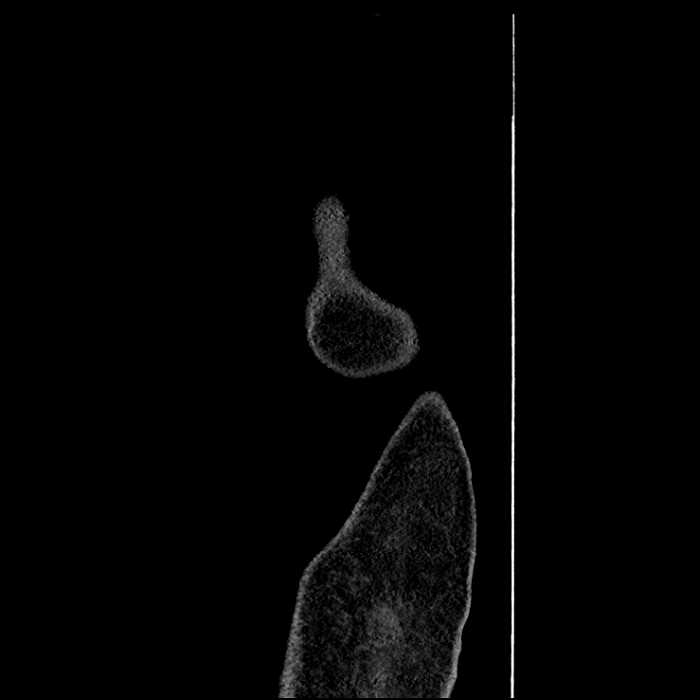

• Ankylosis of both sacroiliac joints

Hepatic abscess showing the double target sign with low density internally surrounded by a thin inner enhancing rim (red arrow) and ill-defined outer low density rim (yellow arrow). Blue arrow indicates an internal septation. Red arrows: additional smaller subcapsular abscesses. Red arrow: focal contained perforation associated with diverticulitis.